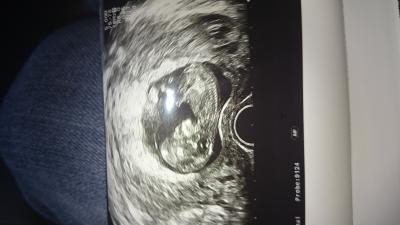

Bin soooo glücklich :-) Baby ist heute bei 12+0 5,7 cm groß und sehr aktiv

Bild zu FA-Termin :-) - Forum für August - Mamis

Wow. Super bild. Da sieht man ja voll die Wirbelsäule! super... genieße das Glücklich sein...